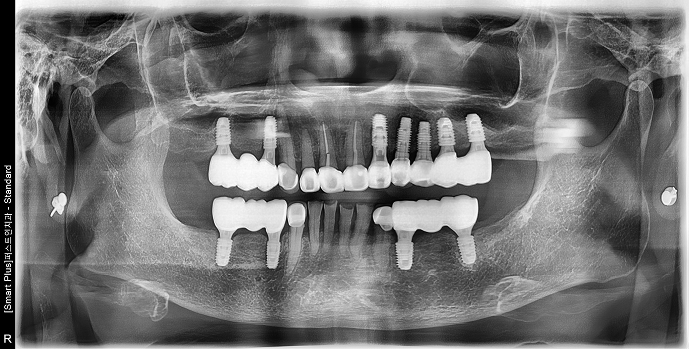

• 80대 여성 | 틀니불편 | 임플란트, 상악동거상술 | 치료기간 7개월

Before 2024.08.06

After 2025.03.20